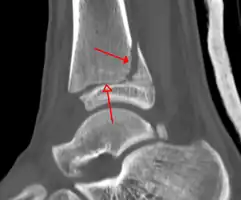

-

A triplane fracture of the ankle as seen on plain X-ray -

A triplane fracture of the ankle as seen on CT -

A triplane fracture of the ankle as seen on CT